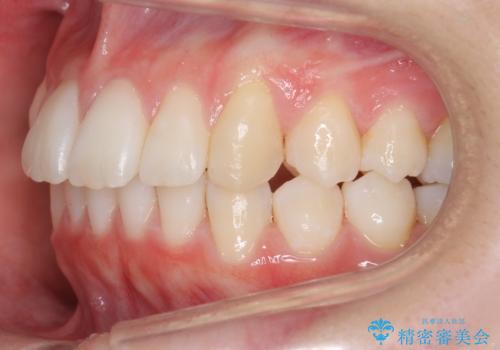

歯を抜かないで出っ歯を治したい

- 前歯が出ていることを主訴に来院。

歯を抜かずにマウスピース矯正をご希望でした。

歯と歯の間をわずかに削り、歯並びを少し横に拡大して並べました。

奥にすき間がなかったため後ろには下げていません。

沢山ひっこめるには4本抜歯でワイヤーの選択肢もありましたが、抜かないでできる範囲をご希望されました。

とがった形の歯列を整えるだけでもだいぶ印象は変わると思います。

今回歯列を広げた結果、上顎犬歯の歯肉は多少退縮しています。